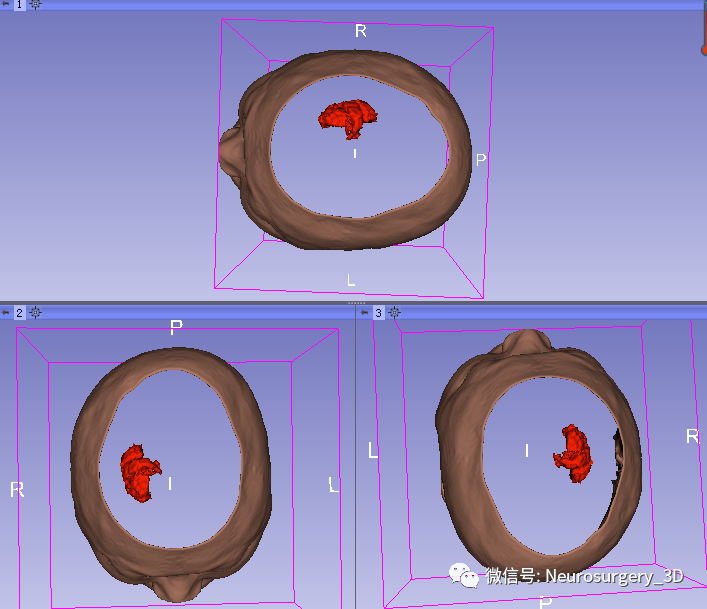

运算后结果

放大后不同视角观察